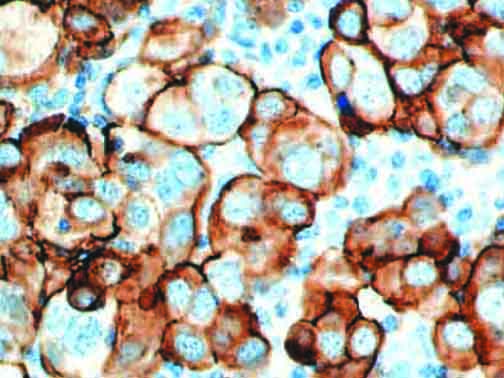

The first cytokines released are interleukin 1β (IL-1β) and tumor necrosis factor-α (TNF-α), which attract a variety of circulating white blood cells (WBCs) to the infection site, including neutrophils, monocytes, macrophages, and natural killer (NK) cells. This response, along with the antipathogenic chemicals released by these cells (i.e., complement), comprise the innate immune response. These cells directly attack the invading pathogen and also release additional cytokines, chief among them interleukin-1 and 6 (IL-6). IL-6 is essential for invoking the adaptive immune response, which calls T-cells, B-cells, and T helper (Th) cells to the infection site. IL-6 also stimulates further recruitment, proliferation and activation of macrophages.

It is the ICU physician who is most likely to witness one of the deadliest manifestations of the abnormal immunological response, the cytokine storm syndrome (CSS). This response is also referred to by some as the cytokine release syndrome (CRS). CSS is characterized by continuous activation and expansion of macrophage and lymphocyte populations, which secrete large amounts of cytokines, causing the cytokine storm. This massive cytokine release is akin to hemophagocytic lymphohistiocytosis (HLH) disease, a syndrome characterized by initial unchecked and persistent activation of cytotoxic T lymphocytes and NK cells.

This activation induces inflammatory monocytes to highly express IL-6, starting a localized and then systemic cascade effect that results in hyperproduction of IL-6, which accelerates the inflammatory process. Because IL-6 also increases vascular permeability, excessive levels cause blood vessels to become very leaky. This, along with clotting factors released from vascular endothelial cells, stimulates the coagulation cascade, resulting in microthrombosis (tiny clots), which leads to ischemia and tissue death of the kidney, intestines, heart, liver, brain and extremities.